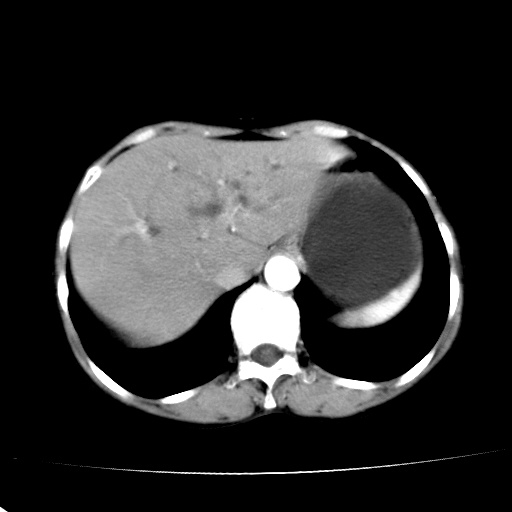

以下是引用jiangjing在2008-6-3 13:36:00的发言:[br]支持 胰头癌------肝内外胆管扩张,胰管扩张,胰头增大,增强见结节状轻度强化影,双管征明显

以下是引用卜一在2008-6-3 14:40:00的发言:[br]支持:胰头癌!(肝内外胆管扩张,胆囊高度扩张,胰管扩张,胰头增大,增强见结节状强化,明显低于胰腺强化密度,并明显见双管征)

以下是引用dyqct在2008-6-3 14:54:00的发言:[br]支持 胰头癌伴肝内外胆管扩张,胰管扩张,胰头增大,增强见结节状轻度强化影,双管征明显。肠系膜上静脉已受侵(已不能手术),建议离子植入治疗吧。